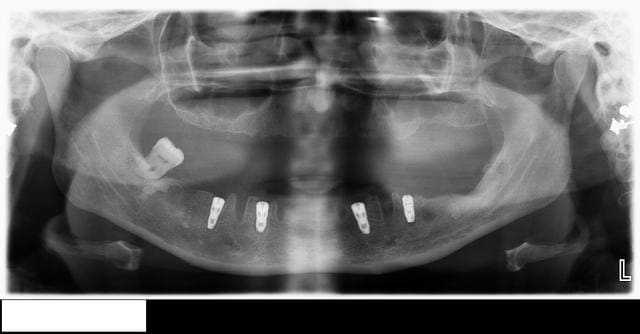

Voici le cas en image

Mon doute portait donc sur la face vestibulaire de l'implant en place de 43.

Implant4.5*11 Astra

Excusez moi pour la pano avec le stellite.